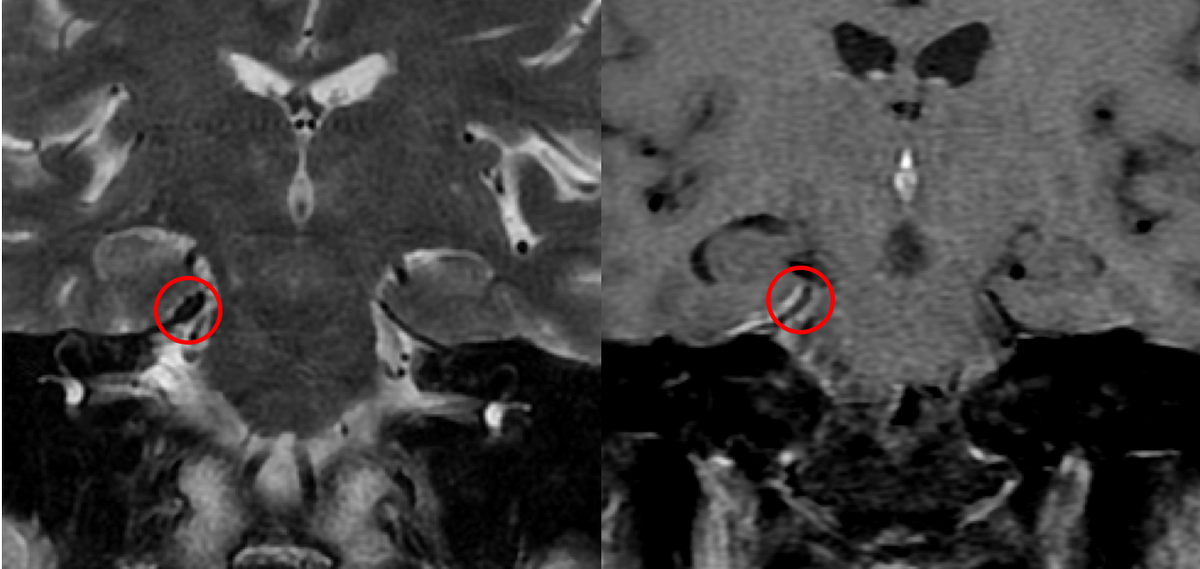

Non displaced trabecular compression fractures are

#easytomiss in osteoporotic#spine;#radres please review soft tissue window for such fractures-surrounding sclerosis due to edema/hemorrhage/compression can make them more visible#FOAMed@NASSspine https://bit.ly/37XAAdH pic.twitter.com/1oGrDA6jz6